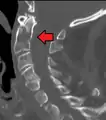

Fractures of the dens, not to be confused with Hangman's fractures, are classified into three categories according to the Anderson Alonso system:

- Type I fracture - Extends through the tip of the dens. This type is usually stable.

- Type II fracture - Extends through the base of the dens. It is the most commonly encountered fracture for this region of the axis. This type is unstable and has a high rate of non-union.

- Type III fracture - Extends through the vertebral body of the axis. This type can be stable or unstable and may require surgery.

A fracture of the base of the dens as seen on CT